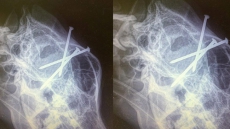

Lost German Shepherd Is Returned To B.C. Owner With Three Nails In Its Head

PRINCE GEORGE, B.C. — The X-rays leave no doubt about what happened, but Maureen Yeo says she still can't fathom why anyone would shoot three construction nails into her dog's head.